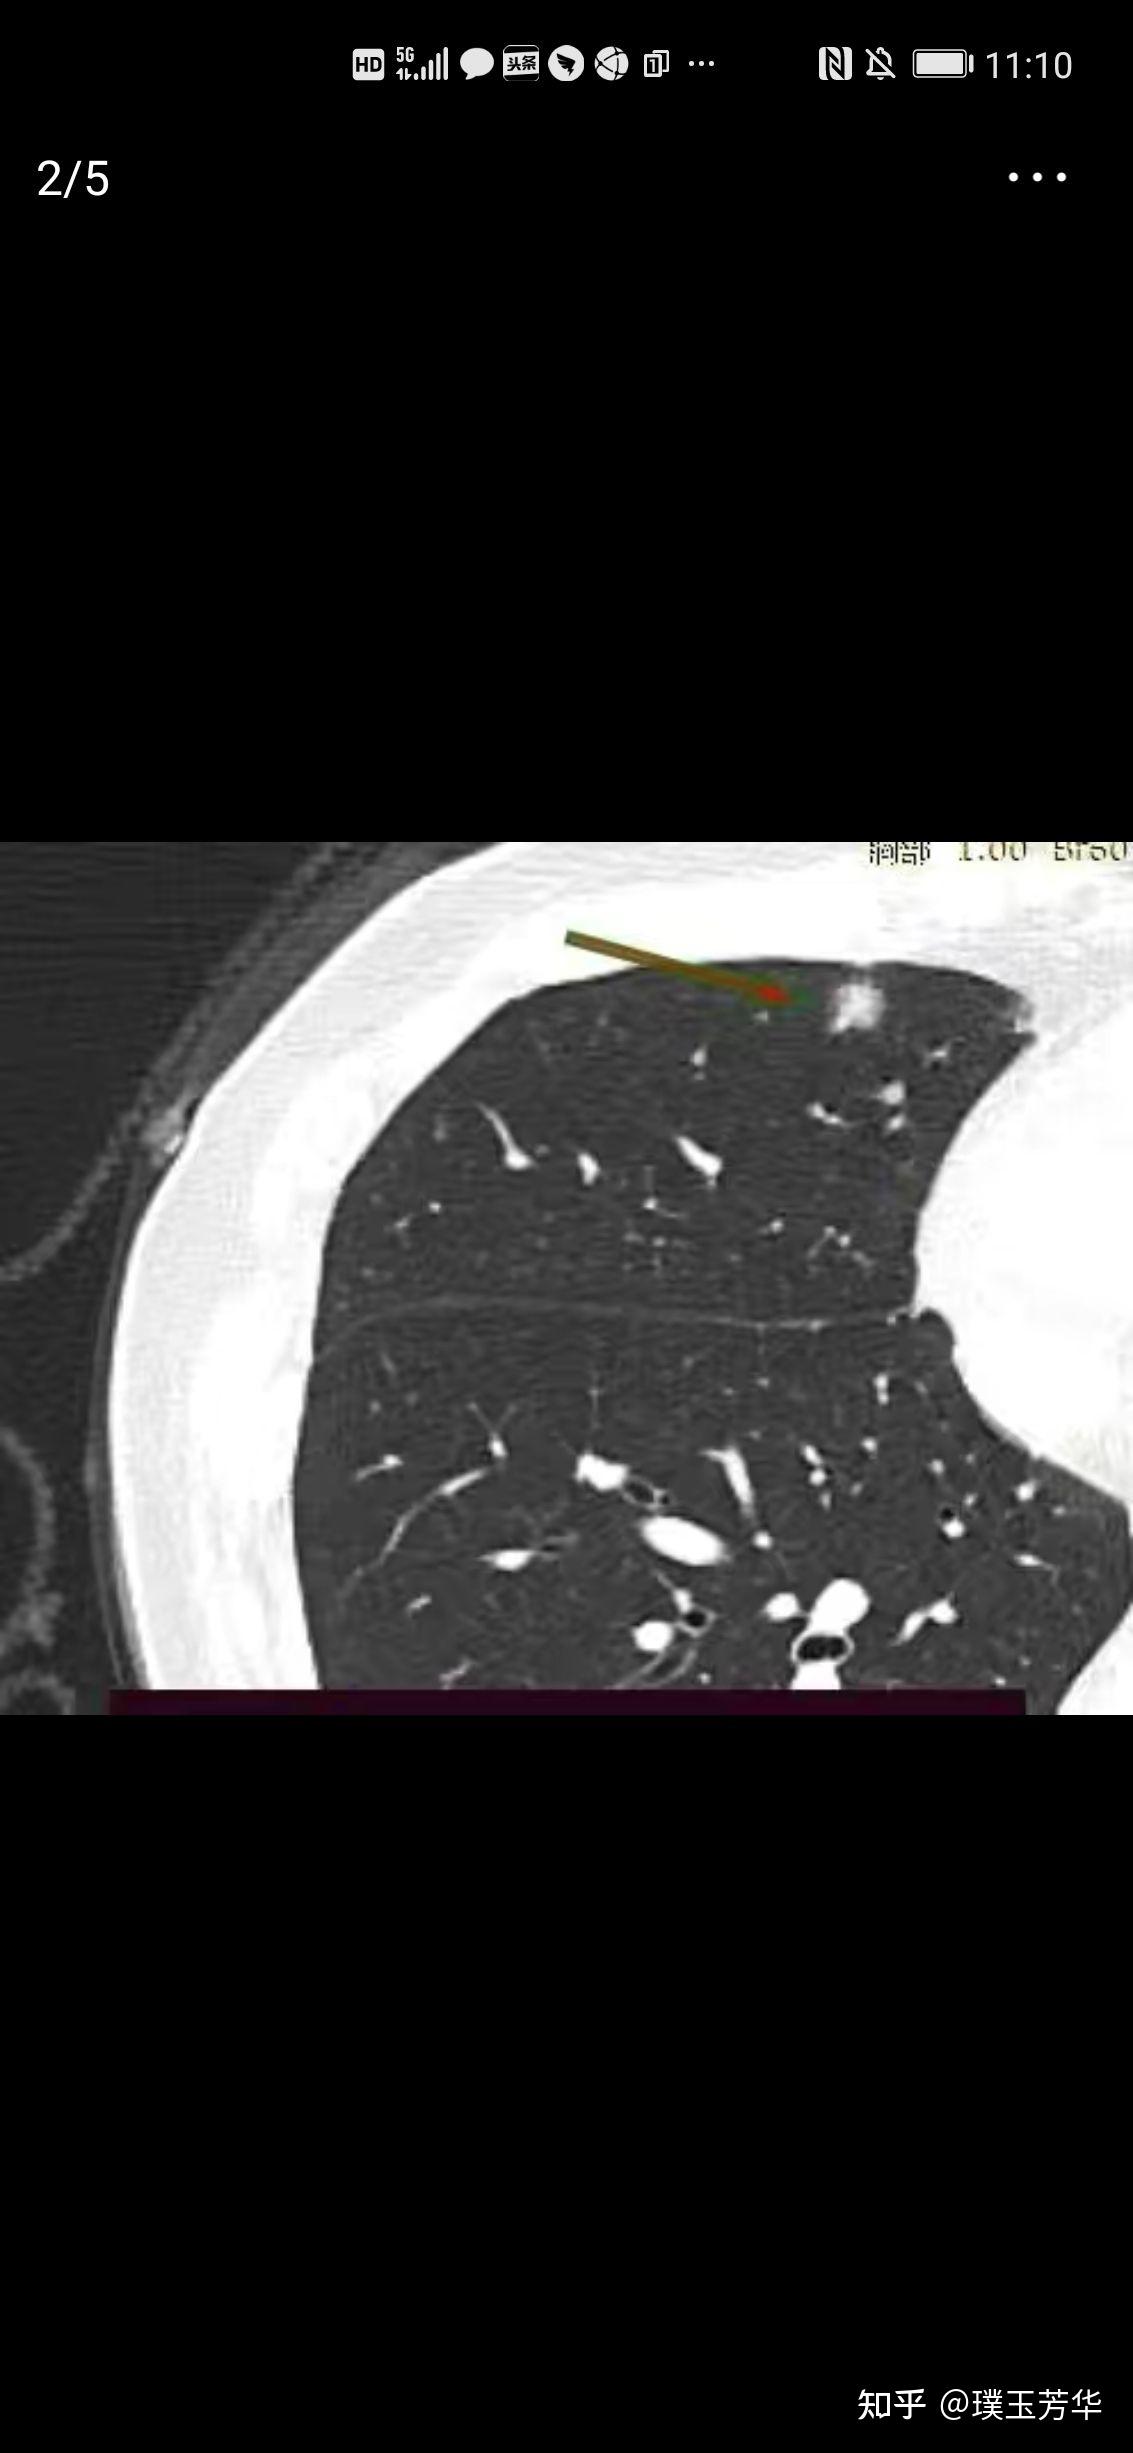

有微乳头亚型和气腔播散,1cm的混合磨玻璃肺结节也可以来者不善